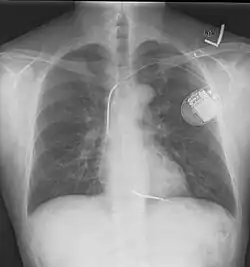

An implantable cardioverter-defibrillator (ICD) or automated implantable cardioverter defibrillator (AICD) is a device implantable inside the body, able to perform defibrillation, and depending on the type, cardioversion and pacing of the heart. The ICD is the first-line treatment and prophylactic therapy for patients at risk for sudden cardiac death due to ventricular fibrillation and ventricular tachycardia.[1][2]

The process of implantation of an ICD system is similar to implantation of an artificial pacemaker. In fact, ICDs are composed of an ICD generator and of wires. The first component or generator contains a computer chip or circuitry with RAM (memory), programmable software, a capacitor and a battery; this is implanted typically under the skin in the left upper chest. The second part of the system is an electrode wire or wires that, similar to pacemakers, are connected to the generator and passed through a vein to the right chambers of the heart. The lead usually lodges in the apex or septum of the right ventricle.[7]

Just like pacemakers, ICDs can have a single wire or lead in the heart (in the right ventricle, single chamber ICD), two leads (in the right atrium and right ventricle, dual chamber ICD) or three leads (biventricular ICD, one in the right atrium, one in the right ventricle and one on the outer wall of the left ventricle). The difference between pacemakers and ICDs is that pacemakers are also available as temporary units and are generally designed to correct slow heart rates, i.e. bradycardia, while ICDs are often permanent safeguards against sudden life-threatening arrhythmias.

Initially ICDs were implanted via thoracotomy with defibrillator patches applied to the epicardium or pericardium. The device was attached via subcutaneous and transvenous leads to the device contained in a subcutaneous abdominal wall pocket. The device itself acts as an electrode. Most ICDs nowadays are implanted transvenously with the devices placed in the left pectoral region similar to pacemakers. Intravascular spring or coil electrodes are used to defibrillate. The devices have become smaller and less invasive as the technology advances. Current ICDs weigh only 70 grams and are about 12.9 mm thick.